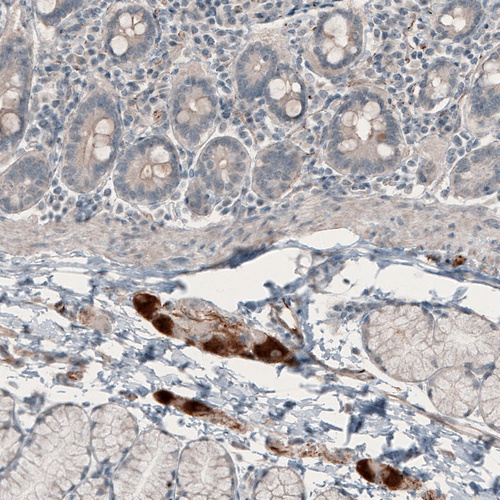

Immunohistochemical staining of human duodenum shows strong cytoplasmic positivity in a subset of cells in the peripheral ganglion.